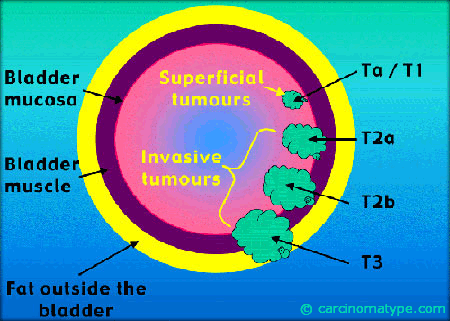

Определение стадии рака мочевого пузыря не менее важно для правильного лечения, чем своевременное диагностирование. Стадия определяется по размеру опухоли, степени ее прорастания в оболочки мочевого пузыря, поражению внутренних органов и лимфатической системы. Однако опухоль мочевого пузыря имеет свои особенности. На первых трех стадиях учитывается исключительно степень прорастания опухоли в оболочки пузыря: подслизистую, слизистую, серозную и подмышечную. Еще один способ определить стадию заболевания — оценить наличие и количество метастазов.

Если у вас определили рак мочевого пузыря, то возможны следующие способы лечения. Выбор метода лечения зависит от степени распространения онкологии. Опухоль мочевого пузыря условно можно разделить на инвазивную и неинвазивную. Неинвазивный располагается на поверхности слизистой мочевого пузыря. А инвазивный прорастает в мышечную оболочку и может распространиться дальше.